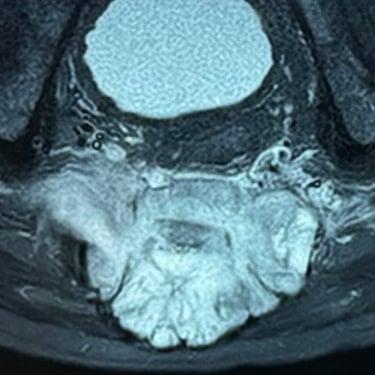

Sarcoma Sacro: Citorreducción Tumoral y Descompresión Nerviosa

El sarcoma sacro es una neoplasia poco frecuente y de manejo complejo que puede generar dolor severo, alteraciones neurológicas y compromiso de la movilidad por afectación de las raíces nerviosas sacras. El tratamiento quirúrgico mediante citorreducción tumoral tiene como objetivo disminuir el volumen del tumor, mientras que la descompresión nerviosa permite aliviar la presión sobre las estructuras neurológicas comprometidas. Este abordaje busca mejorar el control del dolor, preservar la función neurológica y optimizar la calidad de vida del paciente. La planificación cuidadosa y el manejo multidisciplinario son fundamentales para obtener mejores resultados clínicos.